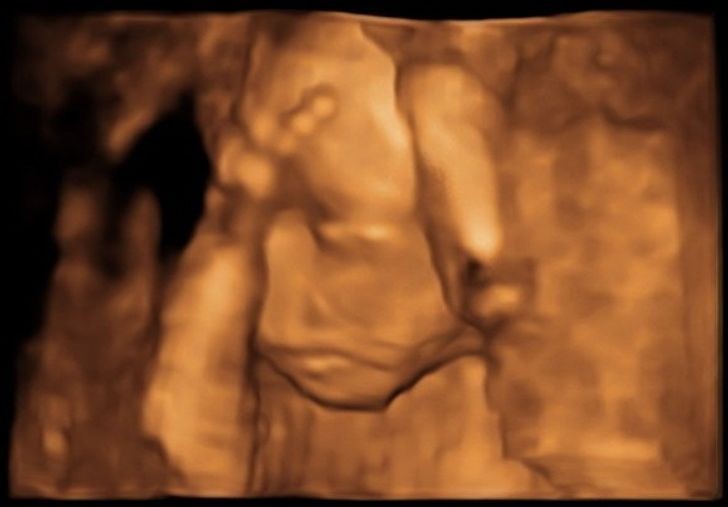

12. "Zażartowałem w trakcie USG. Niestety, mój syn najwyraźniej podziela poczucie humoru swojej matki."